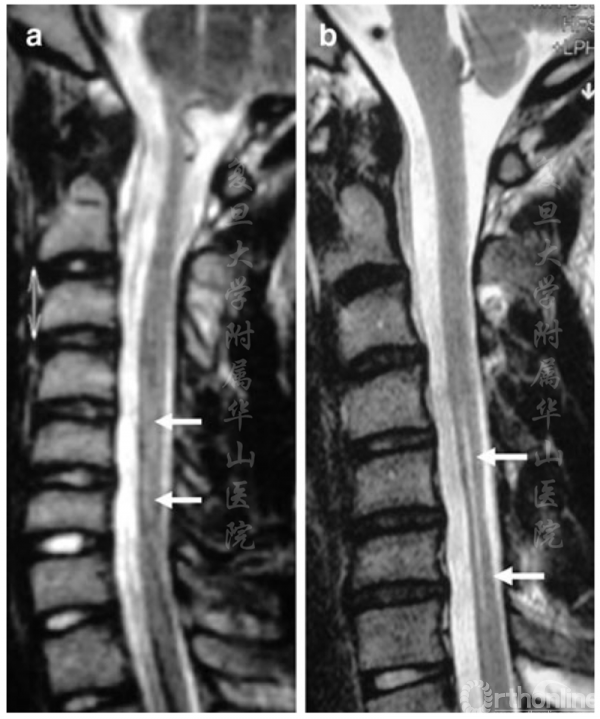

图1 MRI矢状面T2相 a.首次入院时进行的MRI检查显示C5-C6节段脊髓轻度高信号。b.四年后,出现了节段性萎缩和更明显的高信号

MRI检查显示,C5-C6节段脊髓存在轻度肌萎缩及T2加权相脊髓前角高信号,右侧更为明显(图1a)。静脉注射造影剂后可见中等程度增强。患者被诊断为平山病,随后接受了屈颈位及中立位的磁共振检查。屈颈时存在硬膜后壁的前移和硬膜后方间隙的扩大,与平山病的诊断标准一致[3-5]。建议患者使用颈托并每年随访,包括EMG和MRI评估。

从2003年到2007年,患者的临床状况一直稳定,尽管EMG显示症状略有恶化,但MRI没有变化。2007年,临床、电生理和影像学状况逐渐恶化(图1b),因此考虑手术治疗。